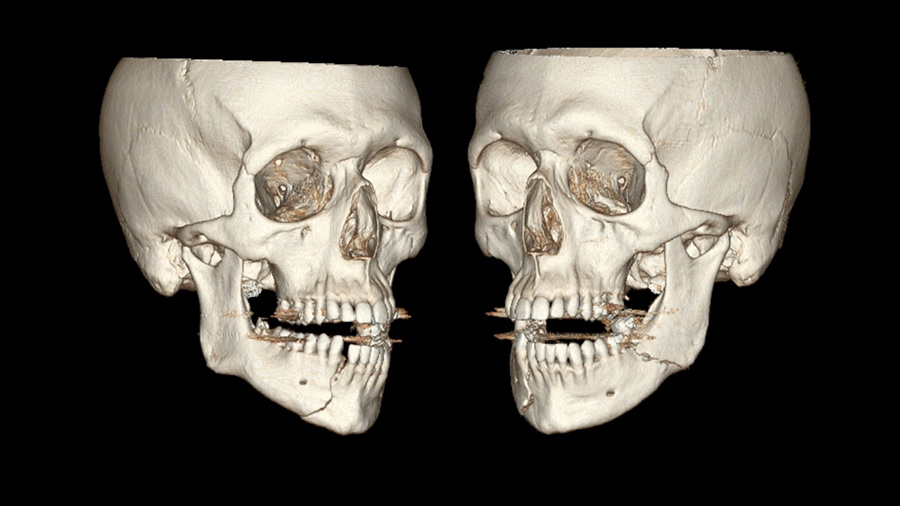

But no grossly loose teeth. Maxilla stable, the rest of the neurovascular and craniofacial examination is completely normal. What you're looking at is an mandible fracture. How did you describe this - this fracture pattern that you see in front of you?

Dr. Susarla: As you know, the first is to think is the fracture pattern concordant with the patient's clinical symptoms. The description that you provided about paresthesia and kind of the lower facial distribution that would be expected in a patient with mandibular injury because of the transit of the inferior alveolar nerve. And also coincident with the description is that gingival laceration between the right lateral incisor and the canine.

The imaging shows a right parasymphyseal fracture and a left mandibular angled fracture. And the concordance of the imaging findings with the clinical exam should be reassuring to you. Sometimes when there's a discrepancy between the two, you have to reconcile that. And one of the most important points about mandible fractures that I've learned over time and we try to stress to our own trainees is when you see a patient with what is presumed a unilateral mandible fracture, it's your job to rule out a bilateral or counter coup injury because they often occur in pairs, as you see in this case.

Now, this fracture orientation at the angle is favorable because the angulation of the fracture runs perpendicular to the masseter muscle, so you can see on the imaging that the fracture is generally nondisplaced. A subtle finding on the imaging, which is really important, is that there is a tooth in the way of the fracture which appears to be outside of the arch alignment.